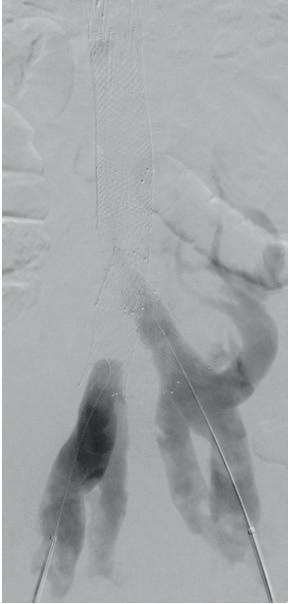

All of which raises the question of treatment modality, and which cases point to which method of re-intervention. In most scenarios, Hemingway outlines, the most effective modality to remove in-stent thrombosis is mechanical thrombectomy with the RevCore thrombectomy catheter (Stryker/ Inari)—except in the setting of couple-ofweeks-old acute stent thrombosis.

associated iliofemoral thrombosis. The IVC and common iliac vein (CIV) stents were thrombosed.

“Both sides had gone down,” Hemingway explains. “One was thrombosed all the way through, the other had a wisp of flow going through it. I took the patient for a venogram and tried aspiration without success, so then tried the RevCore. What we got out was all white, rubberish, fibrotic material. This is someone in whom, had I opted for aspiration thrombectomy, I would have had to reline the whole stent reconstruction. We were able to clean out the stent and send the patient home without any new stents being placed.”

Post-intervention, the patient was noted to have brisk flow on venogram, no thrombus layering on intravascular ultrasound (IVUS), and no further stenting was

Sequential images demonstrate treatment of in-stent thrombosis using the RevCore catheter, showing complete thrombus removal and restoration of luminal patency 1 2 3

RevCore mechanical thrombectomy in action

Hemingway recalls a classic case using the RevCore Thrombectomy Catheter that underlines why the modality is his go-to in these types of scenarios.

The patient was a 35-year-old male who presented with worsening back pain, leg swelling and edema that on imaging appeared to point to an acute DVT. Several years prior, he had undergone thrombectomy, IVC stenting and a bilateral iliocaval reconstruction for chronic IVC occlusion and

required. Now 18-months post-procedure, the patient has sustained full patency and complete symptom resolution.